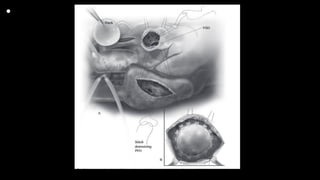

• This still frame image

of a parasternal short

axis view of the

echocardiogram of a

patient with tetralogy

of Fallot demonstrates

the antero-cephalad

deviation of the outlet

septum into the right

ventricular outflow

tract.

• A slightly modified view (a), angled to optimize

imaging of the pulmonary arteries in the patient

imaged to produce Figure 6, reveals significant

hypoplasia of the pulmonary trunk and the

pulmonary arteries, which result from the antero-

cephalad deviation of the outlet septum. The

pulmonary valvar leaflets are not visualized. In panel

b, colour Doppler has been used, and demonstrates

turbulence and acceleration of the flow of blood in

the right ventricular outflow tract, originating at the

level of the deviated outlet septum. The turbulence

continues into the hypoplastic pulmonary trunk and

pulmonary arteries.